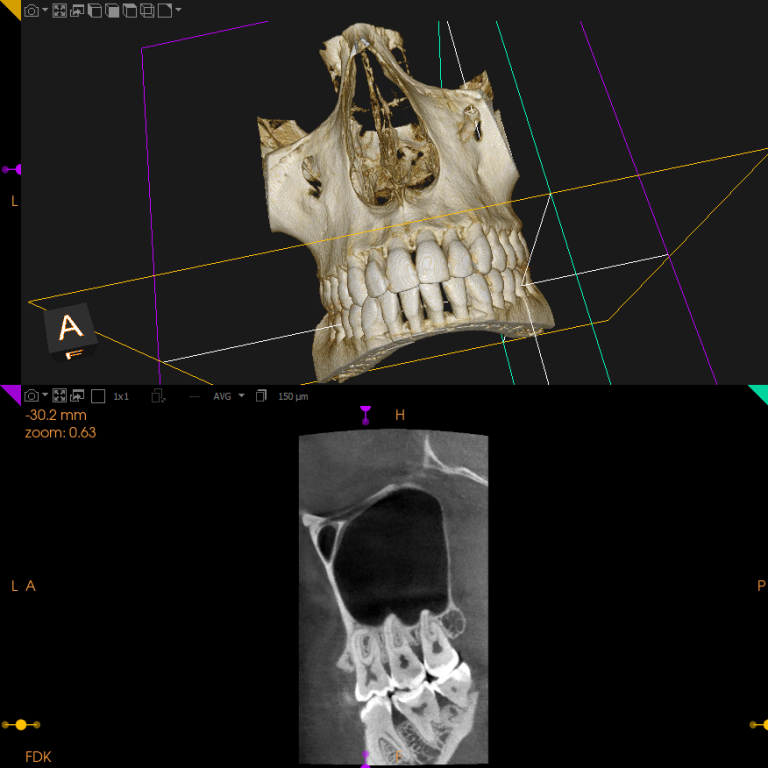

Cone beam

Le cône beam est un examen radiologique en 3D qui permet d'obtenir des images précises des dents, des mâchoires et des structures environnantes